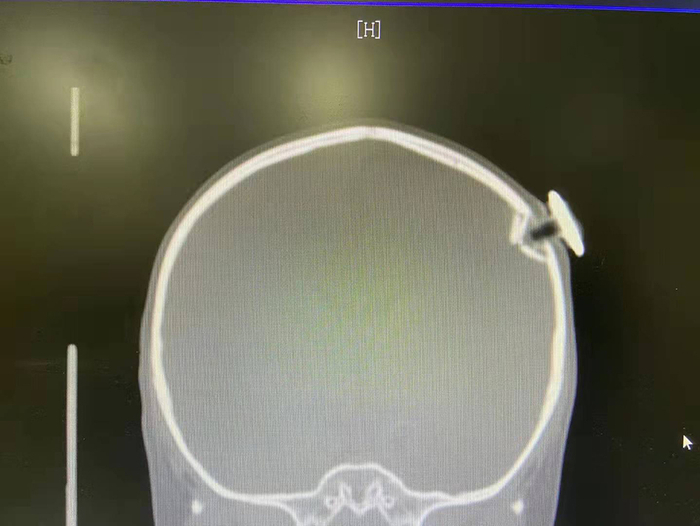

根据CT检查显示,这枚磁力钉撞碎了孩子颅骨,一头扎进大脑约1.3厘米,造成左侧顶骨凹陷性骨折和脑外出血,而且刺破脑膜,差点就损伤了脑部的功能区。